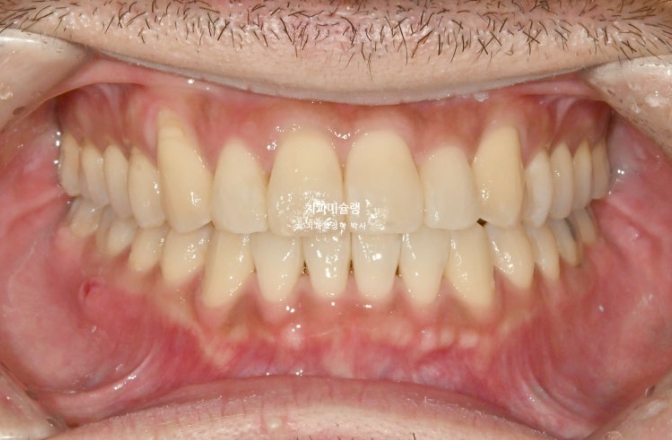

그리고 드디어 치료가 마무리 되었습니다.

25.10

거의 맞아진 중심선

교합은 물샐틈 없는 1급 교합관계를 보입니다.

악궁확장 기간을 포함하여 총 치료기간은 1년 3개월입니다.

중심선의 개선과 덧니의 해소